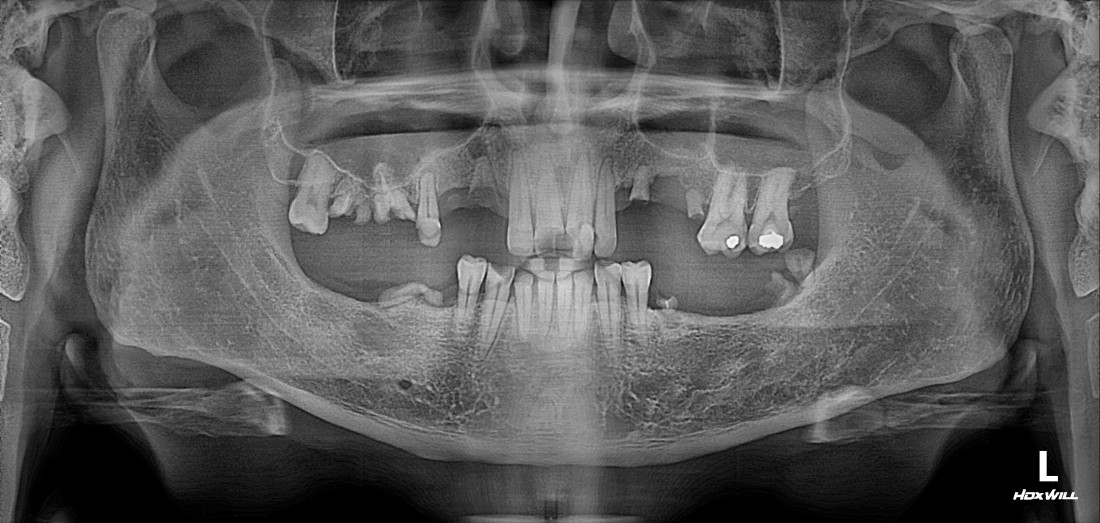

수완동 임플란트 치과에서는

디지털 가이드 임플란트를 통해

자동차가 네비게이션을 따라

정확한 목적지에 도착하듯,

가이드 임플란트를 제작하여

미리 컴퓨터로 모의시술을 진행하고

정확한 위치에 정확한 깊이로

임플란트를 식립하고 있습니다.

![]() | ![]() |

모든 치과에서 가이드 임플란트가

가능한 장비가 갖춰져있는 것이 아니고,

또 치과의사마다 가이드 임플란트 시술경험이

모두 다르기 때문에,

디지털 가이드 임플란트 식립 경험이 풍부한

수완동 임플란트 치과의

구강외과 전문의 대표원장 진료로

성공적인 임플란트를 완성합니다.